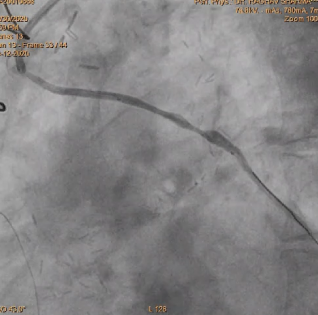

stent was deployed in OM and LCX

After using covered stent perforation was sealed and TIMI 3 flow achieved